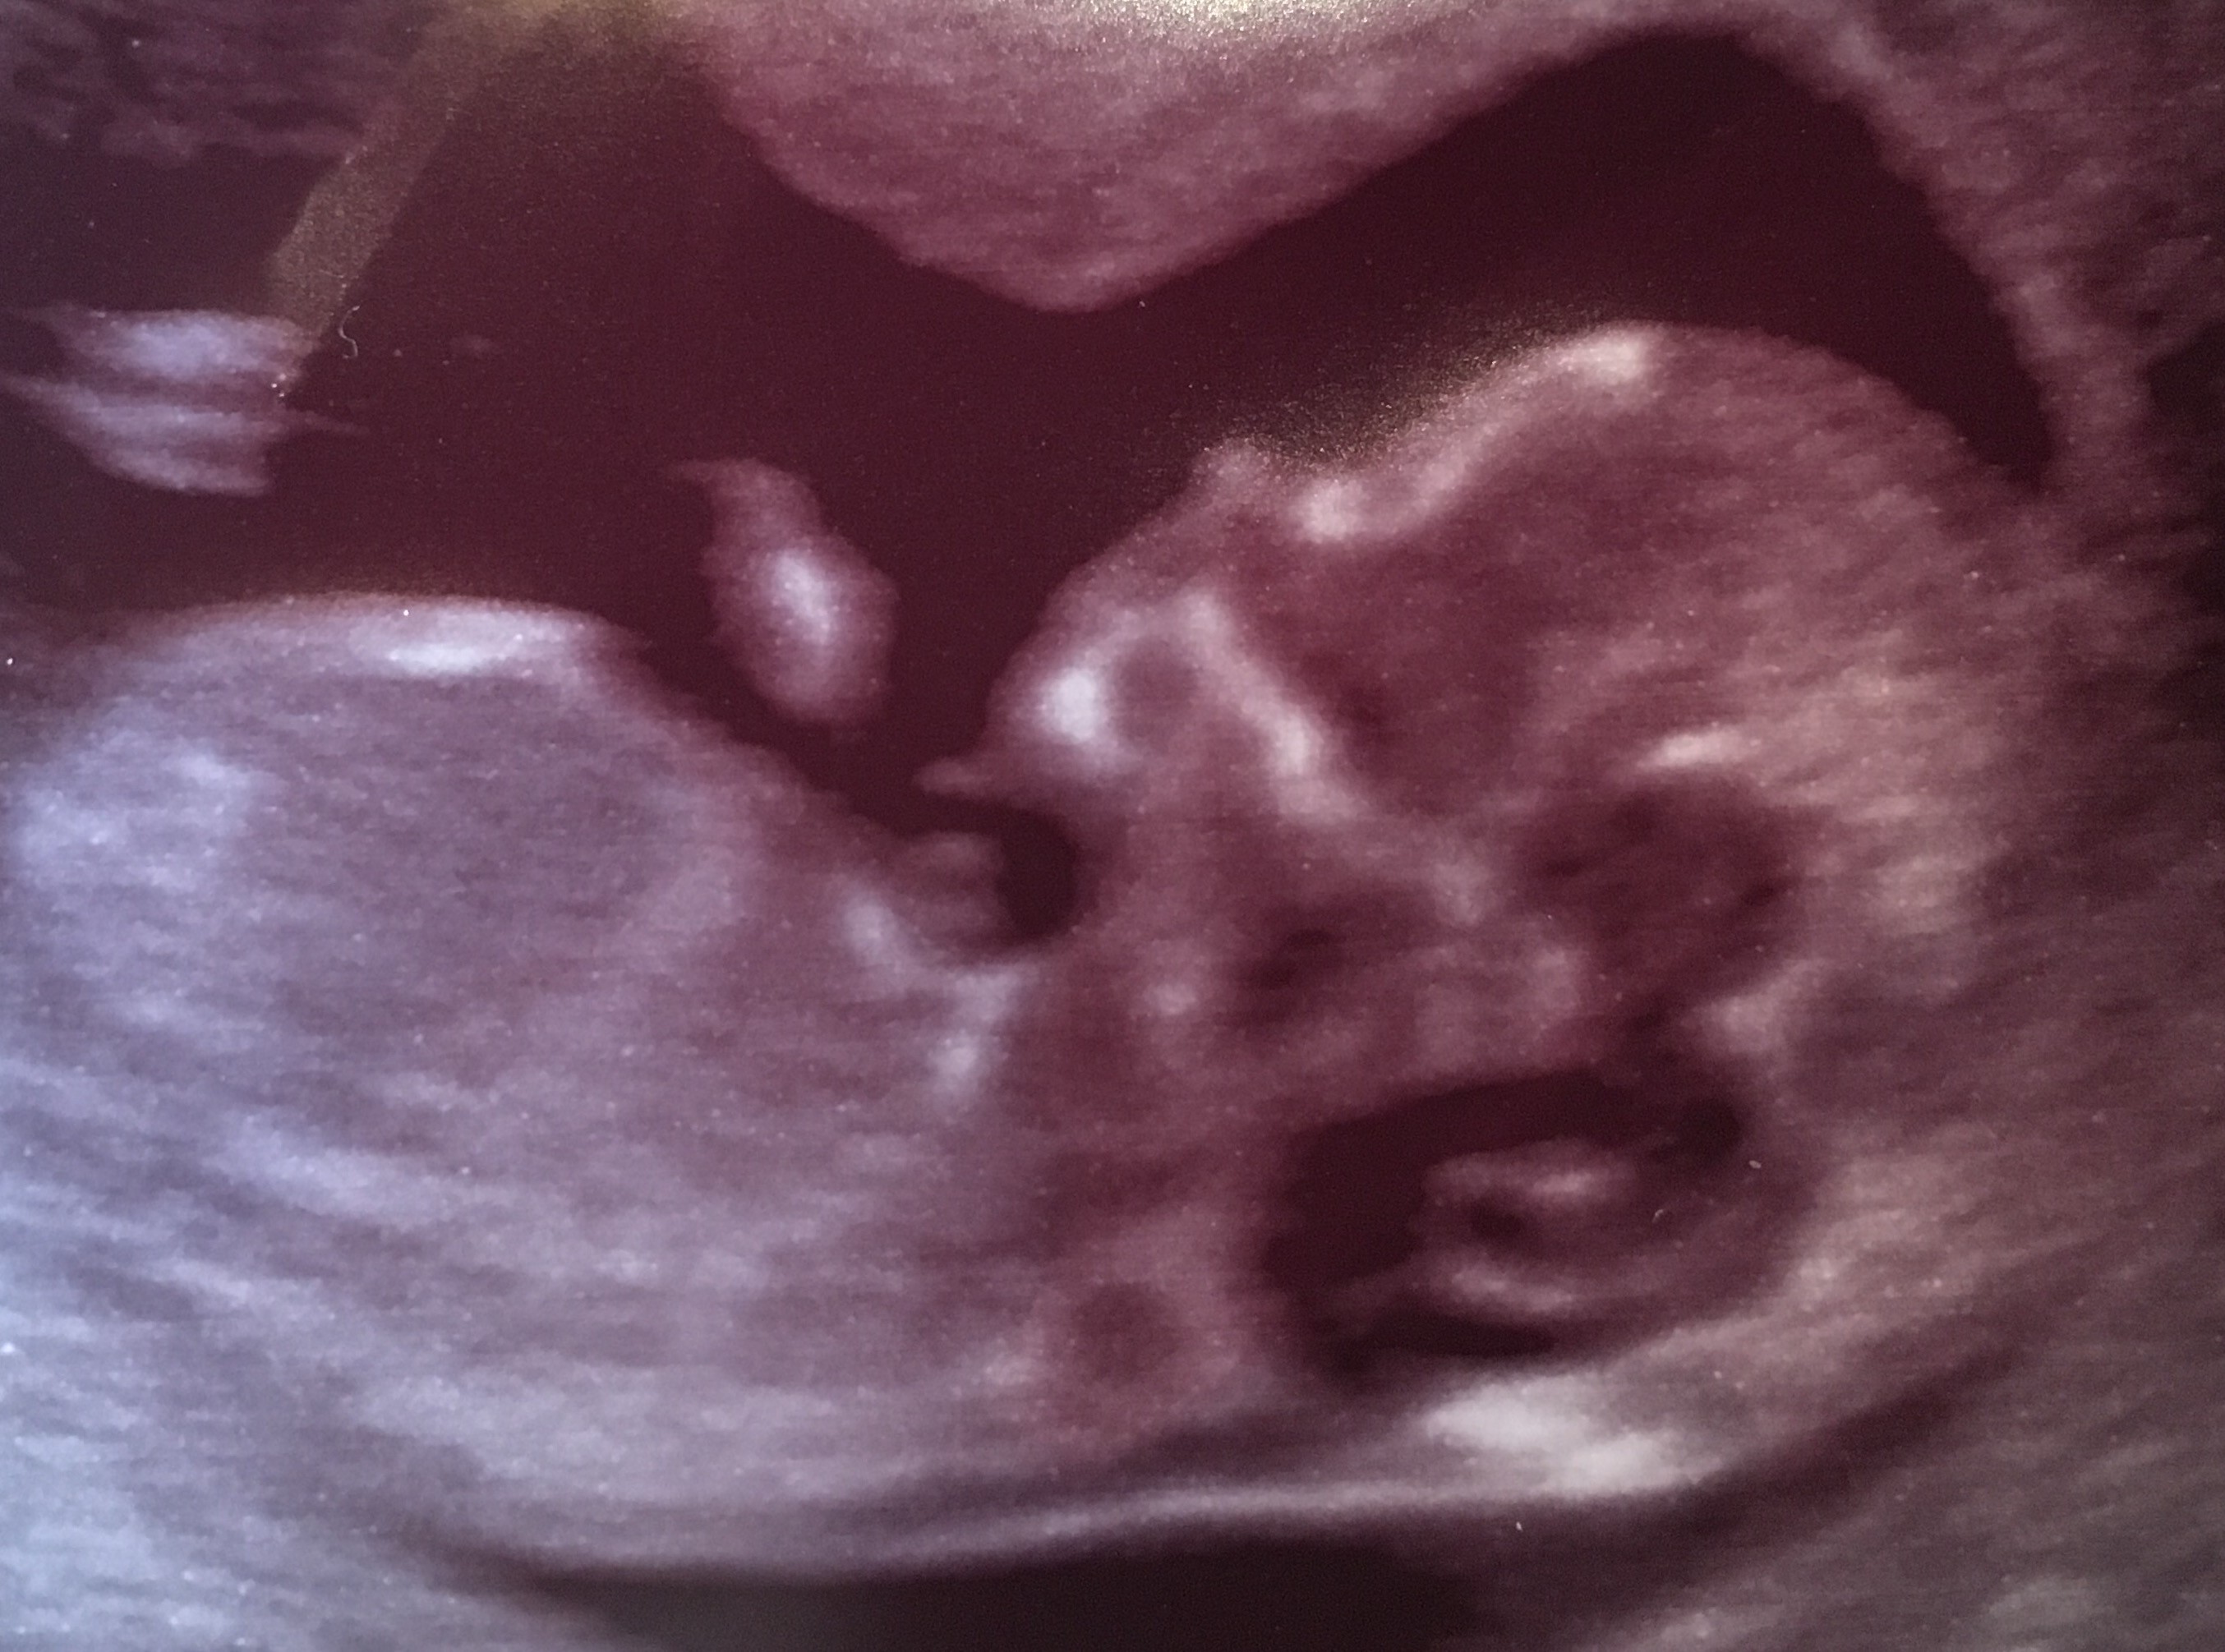

Ale już duże !!!! SuperDziewczyny jestem dzidzi dobrze sie mniewa ma juz ponad 6 cm a mi zaczyna sie 13 tydz

Dziewczyny jestem dzidzi dobrze sie mniewa ma juz ponad 6 cm a mi zaczyna sie 13 tydz

Badania zrobione usg I krew I niby Na wynik mam Teraz czekac jak to jest z tym sydromem zes Downa też czekałyście. Na czym wogole polega to badanie czy ktoś może mi to przybliżyć.